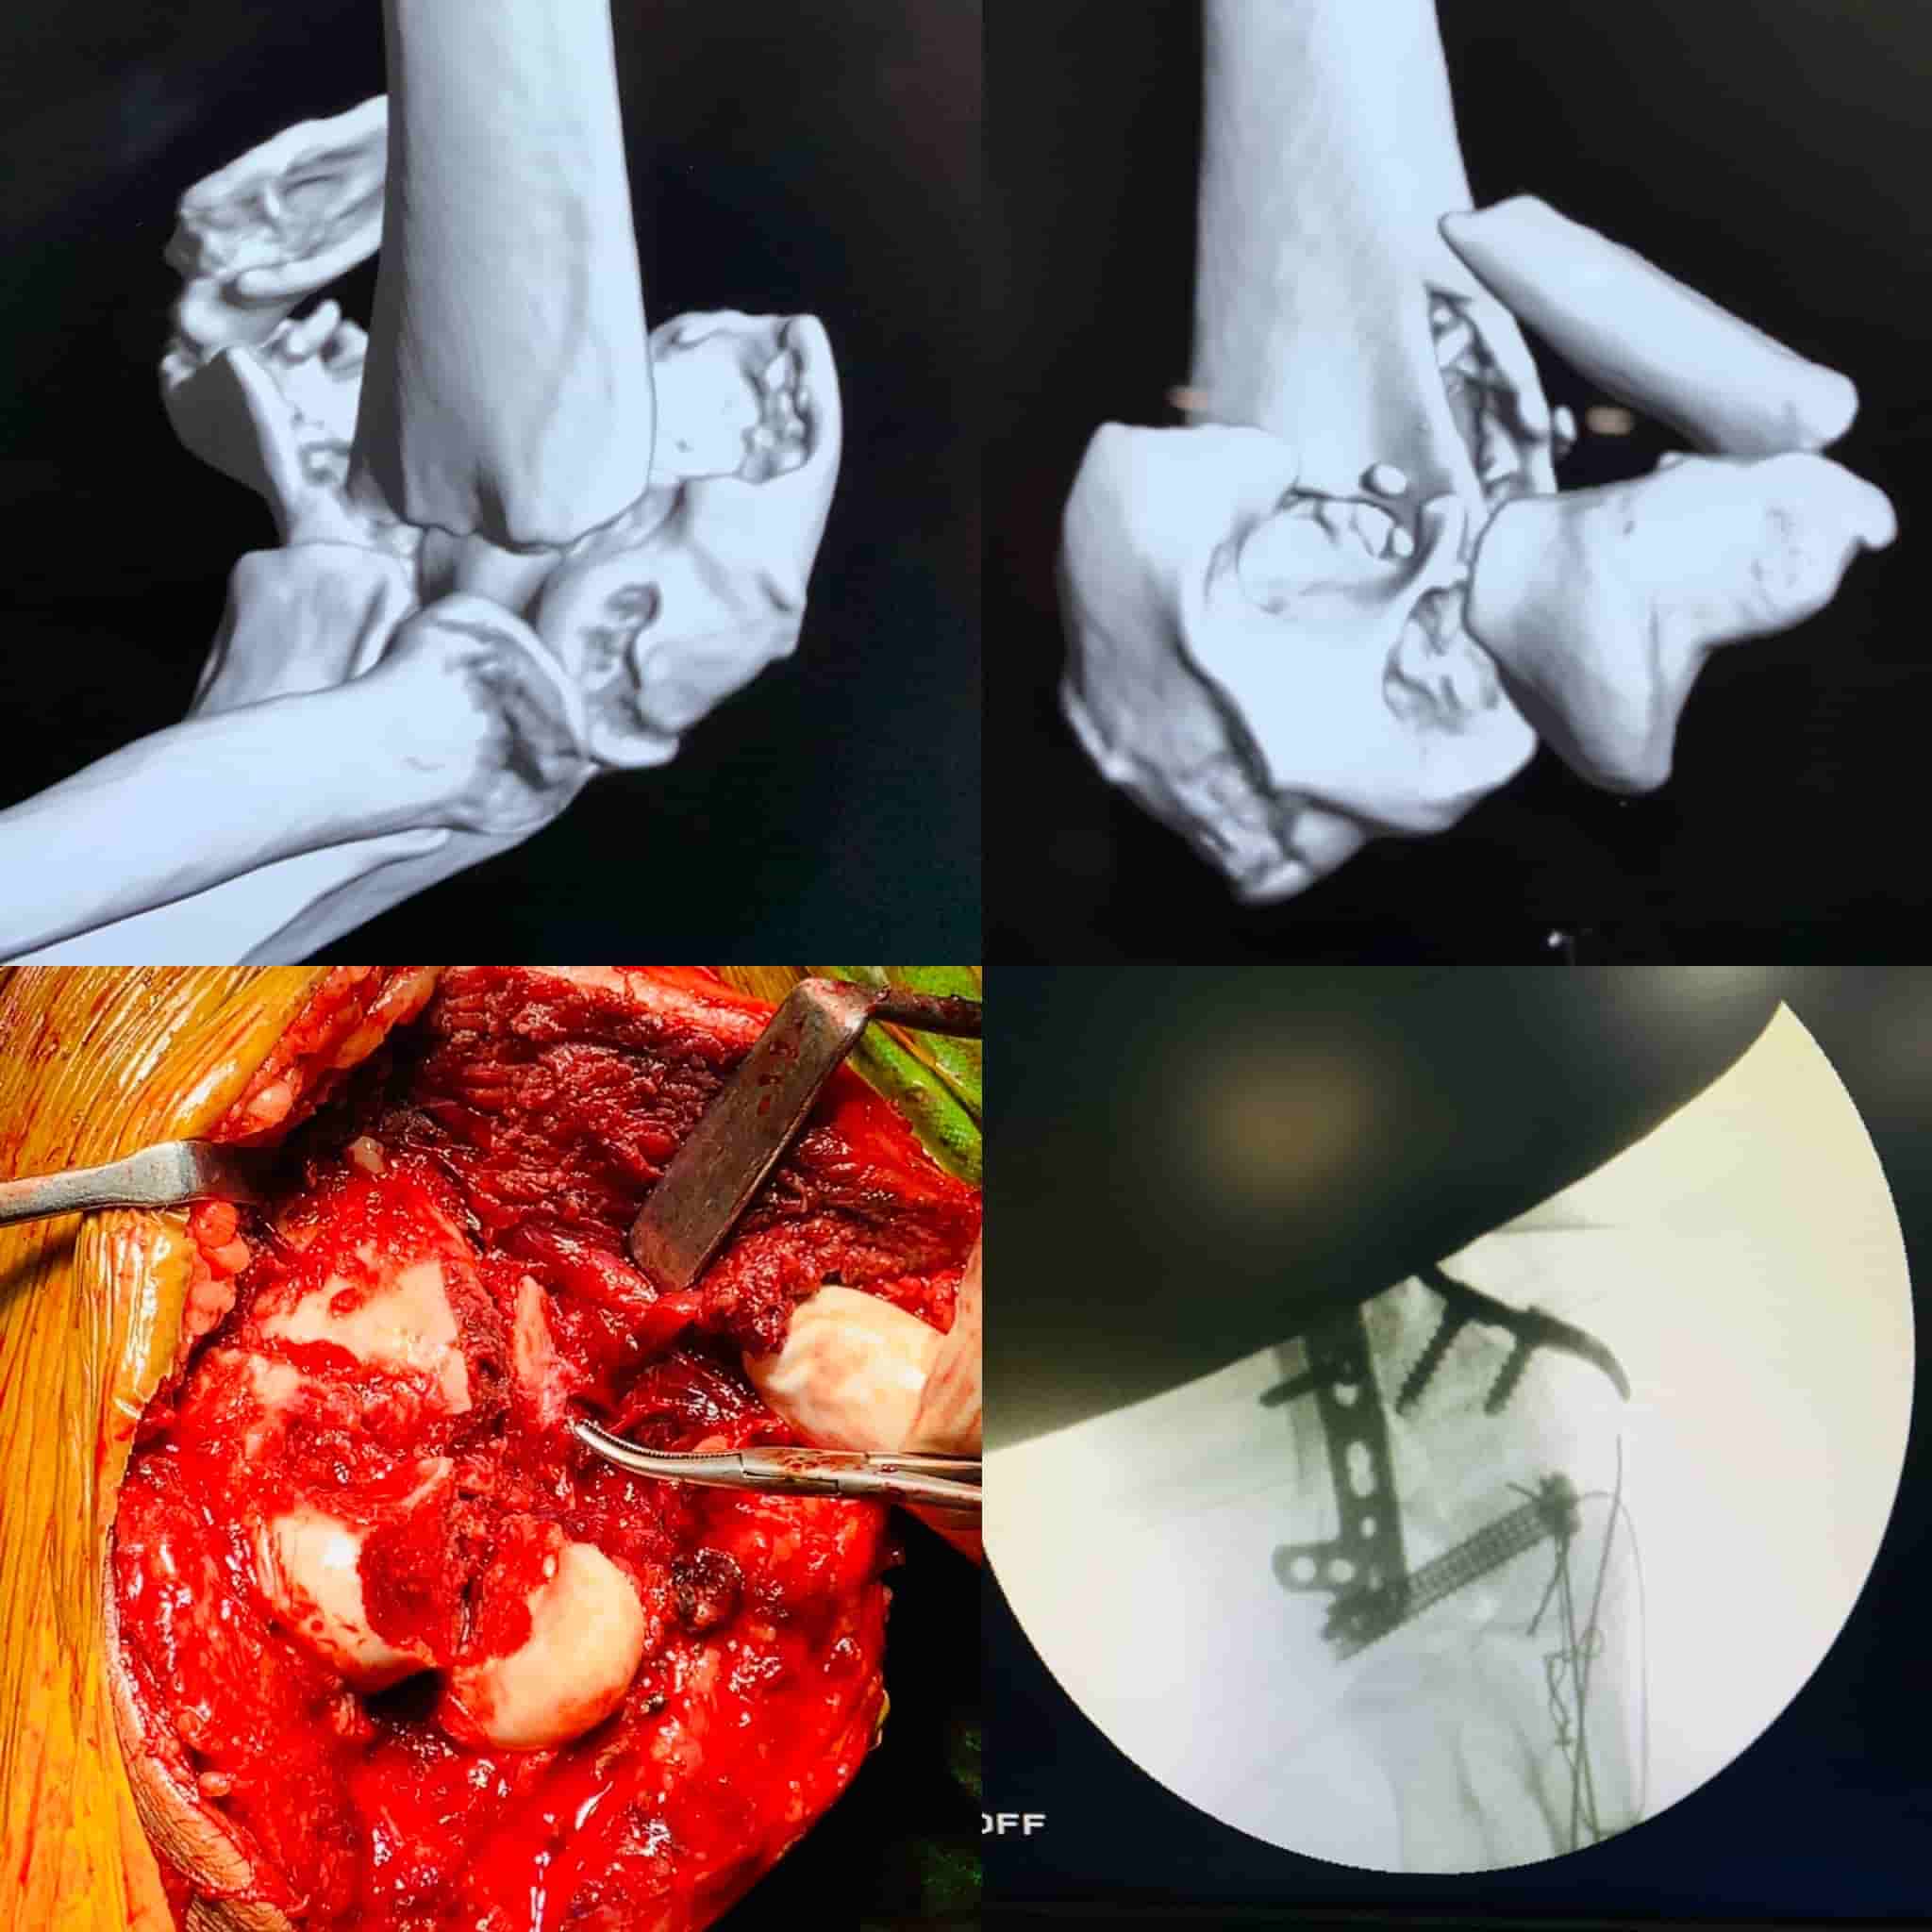

Complex Distal Humerus Comminuted Fracture

Complex Distal Humerus Comminuted Fracture

Complex Distal Humerus Comminuted Fracture

Complex Distal Humerus Comminuted Fracture

Complex Distal Humerus Comminuted Fracture

Complex Distal Humerus Comminuted Fracture

Complex Distal Humerus Comminuted Fracture

Complex Distal Humerus Comminuted Fracture

Complex Distal Humerus Comminuted Fracture

Complex Distal Humerus Comminuted Fracture

Complex Distal Humerus Comminuted Fracture

Complex Distal Humerus Comminuted Fracture

Complex Distal Humerus Comminuted Fracture

Complex Distal Humerus Comminuted Fracture